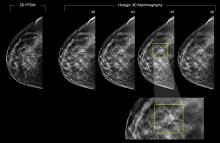

AI is also helping simplify complex tasks and help reduce the reading time on involved exams. One example of this is in 3-D breast tomosythesis with hundreds of images, which is rapidly replacing 2-D mammography, which only produces 4 images. Another example is automated image reconstruction algorithms to significantly reduce manual work. AI also is now being integrated directly into several vendors' imaging systems to speed workflow and improve image quality.